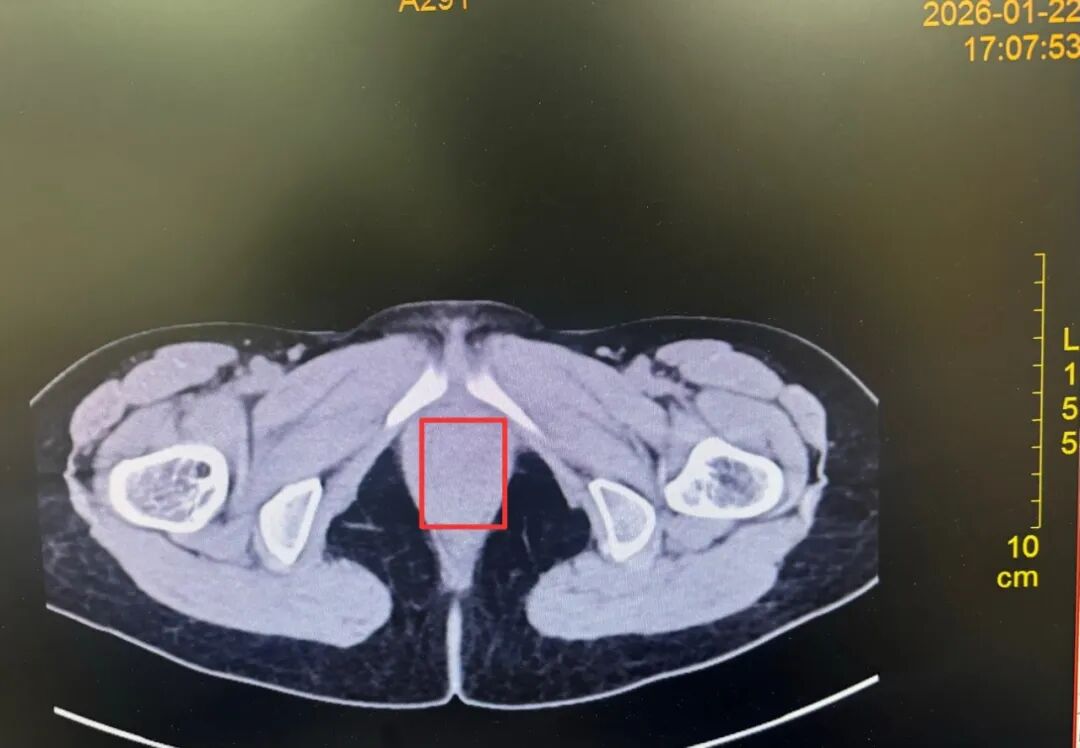

为进一步明确诊断,方松山主任为李女士安排了 CT 扫描。

【术前影像关键图】

三年之「坠」终解除——异物取出

术前 CT 显示存在异常影像